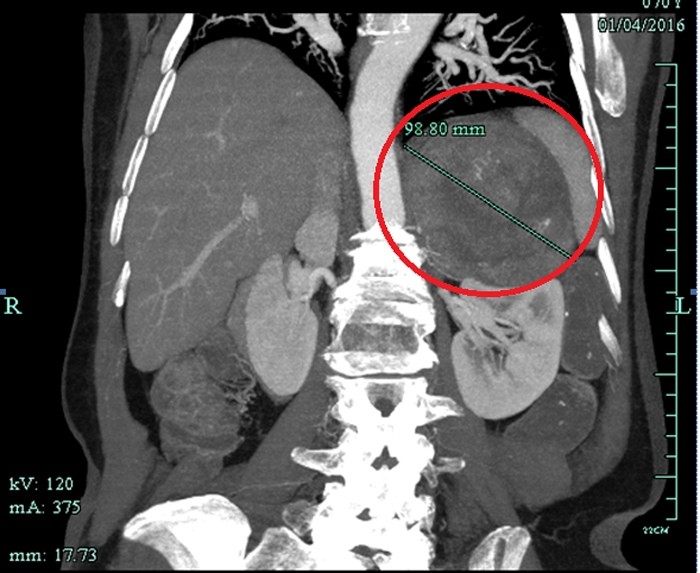

CT檢查意外發(fā)現(xiàn)巨大腫瘤

??? 原來(lái),朱老太與高血壓相伴已經(jīng)有20多年了,一直服用降壓藥,而且血壓忽高忽低不穩(wěn)定。一個(gè)多月前,因?yàn)橹匕Y肺炎在當(dāng)?shù)蒯t(yī)院住院,行胸部CT檢查的時(shí)候發(fā)現(xiàn)左上腹有一個(gè)十多公分的巨大腫瘤。家人馬上把朱老太送到省城一家大醫(yī)院住院,磁共振檢查后考慮左腎上腺惡性腫瘤,需要做大手術(shù)。家人擔(dān)心老人瘦弱的身體承受不了開(kāi)腹手術(shù),多方打聽(tīng)后得知市人民醫(yī)院泌尿外科做腹腔鏡手術(shù)技術(shù)成熟,就找到了萬(wàn)里軍醫(yī)師。萬(wàn)醫(yī)生初步診斷為左腎上腺嗜鉻細(xì)胞瘤,考慮是惡性腫瘤,雖然腫瘤體積巨大,但能在腹腔鏡下切除腫瘤。

患者CT影像